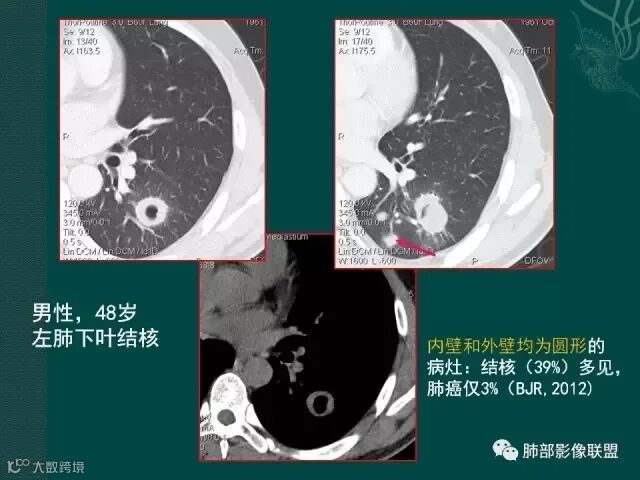

洞壁的血管,腺癌常见,鳞癌较少,结核罕见

结核的破坏力类似于“三光政策”。所到之处,均形成干酪灶,血管都被破坏。